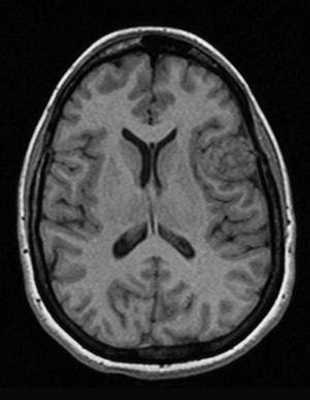

Классический пример МРТ снимков головного мозга показан на рисунках ниже. Магнитно-резонансная томография выполняется в поперечной (или аксиальной - рисунок снизу) и продольной (или сагиттальной — рисунок сверху) плоскостях.

Исследование выполняется в нескольких режимах. Основные из них Т1 и Т2. Изображения, полученные в данных режимах, часто также называют Т1-взвешенными или Т2-взвешенными снимками. Изображения, показанные выше, сделаны в Т1-режиме.

Главное отличие этих режимов - в том, как на снимках отображается жидкость и воздух. В Т1 режиме ткани, содержащие большое количество воды, имеют более темную окраску, в то время как в Т2 режиме они яркие, светлые. Это легко понять, посмотрев на снимки выше - глазные яблоки визуализируются в виде светлых парных округлых образований с одной стороны яркие и светлые, с другой - темные. Следовательно, снимок справа сделан в Т1 режиме, снимок слева - в Т2. Также существует разница в том, как в этих режимах отображается серое вещество головного мозга. В Т2 режиме оно светлее, чем белое вещество.

Как же узнать, есть ли на снимках признаки болезни? Самое главное - запомнить, как выглядит головной мозг здорового человека. Врач, изучая снимки пациентов, постоянно сравнивает их с нормальными снимками, хранящимися у него в голове. Чтобы понять, как это происходит - посмотрите на снимки внизу: